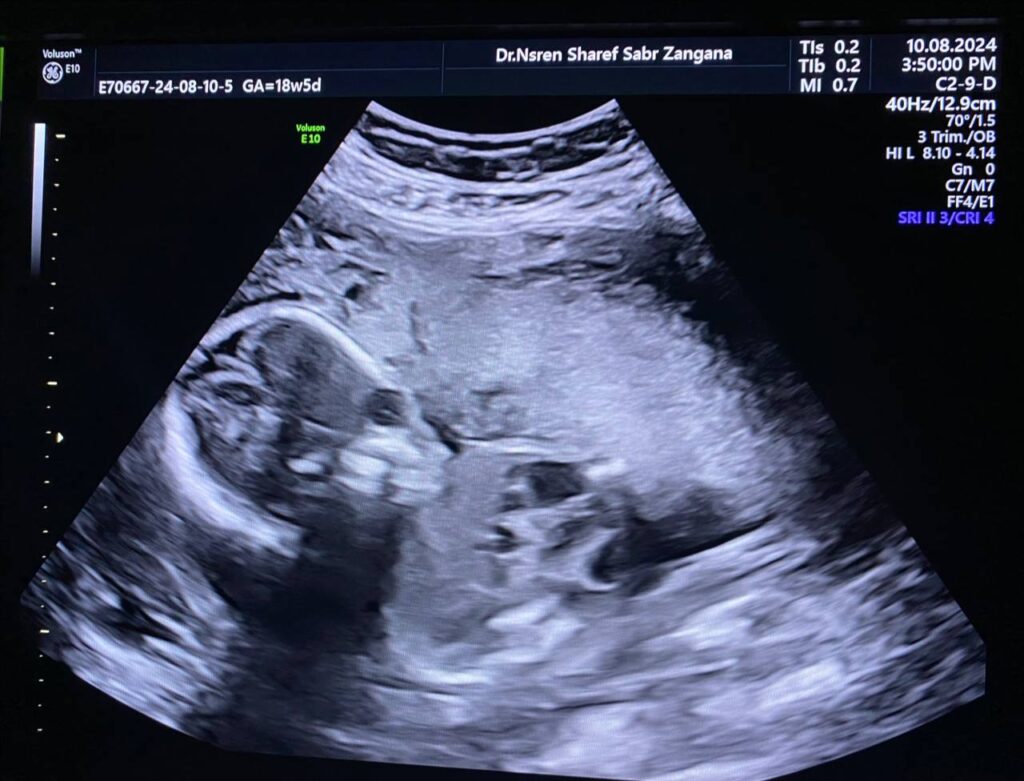

Same fetus when become about 19weeks

Right kidney enlarge in size 34x21x29mm, occupy by numerous

cysts of variable sizes, the largest 13mm , normal left kidney , polycystic ?